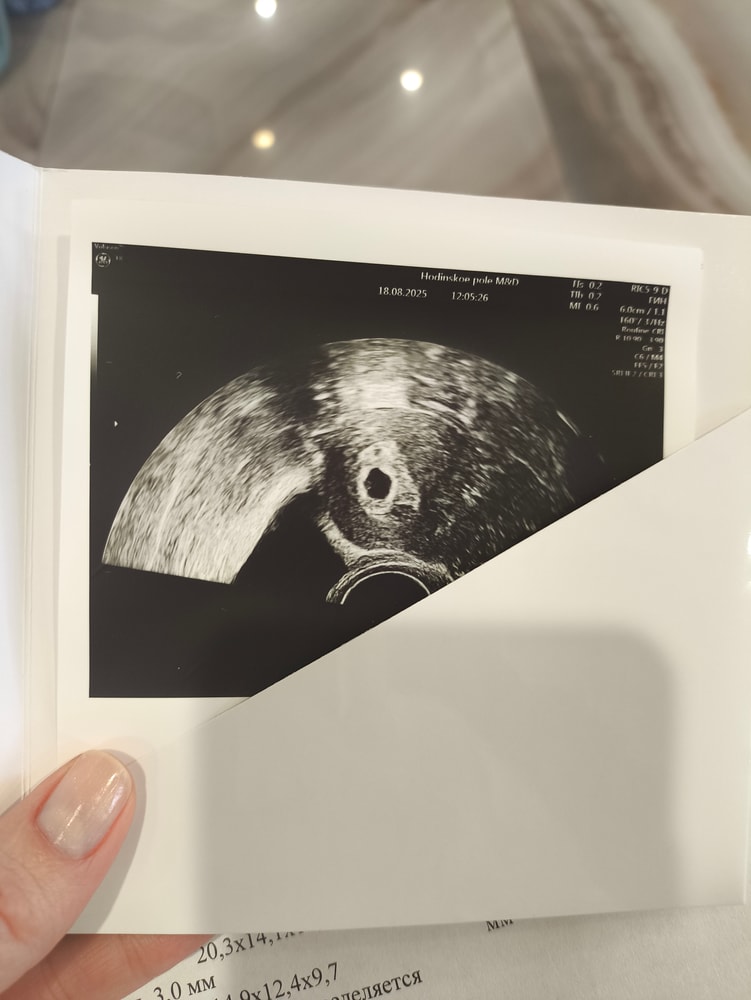

Результаты УЗИ16 ДПП, сходила на первое узи. Волновалась очень, даже ладошки вспотели🥹 Подтвердили маточную беременность - плодное яйцо - 7.95, желточный мешочек - 2.2. Ничего не понимаю в этих размерах, но ре сказала, что все хорошо🫶🏽 так ведь?Следующее УЗИ через 10 дней. Надеюсь, что супруг уже вернётся из командировки, и пойду с ним🥹 бусинка наша❤️